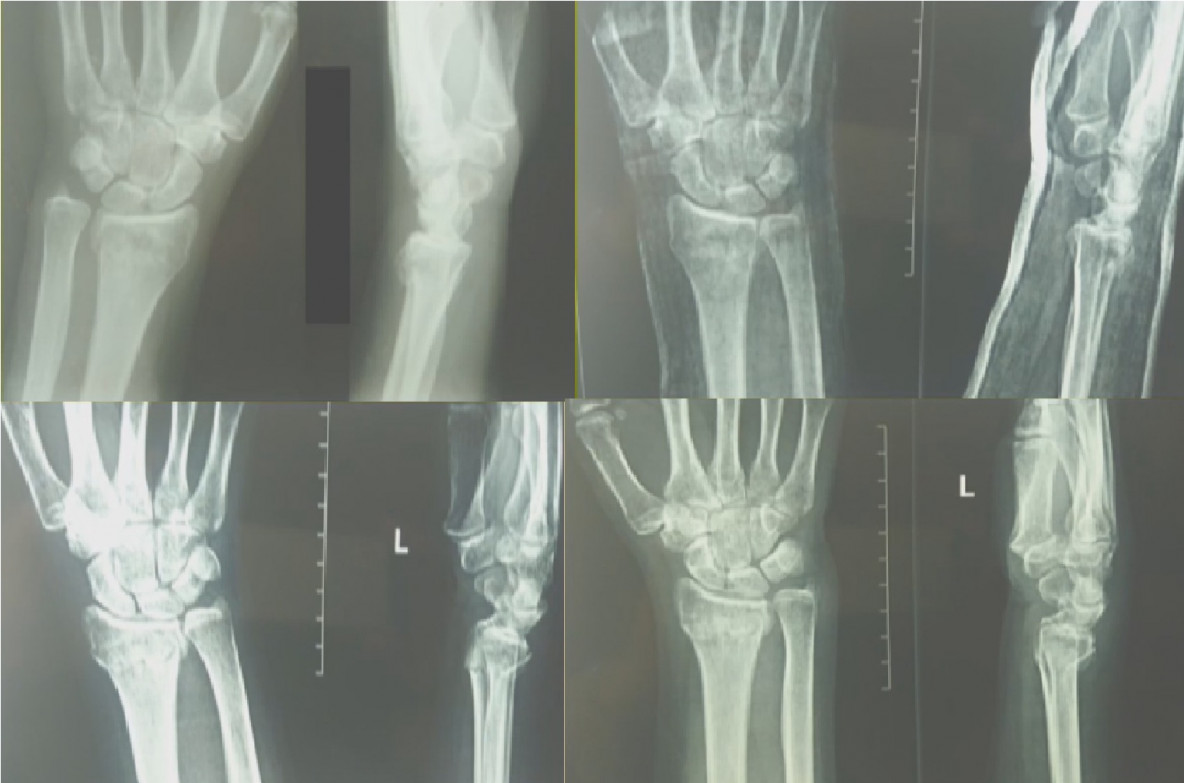

Изображения повреждения костей